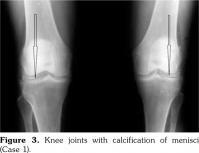

On examination, there was swelling and painful restriction of movement in her right knee. Imaging revealed calcification of cartilage of wrists, knee joints and hip joints although no microscopic confirmation was possible at this stage (Figure 1-4). She was investigated for a possible cause for CC, although investigations to screen for a metabolic cause turned out to be negative with a possibility for hereditary CC.

He had chondrocalcinosis involving the menisci and hyaline cartilage, with predominant patellofemoral joint osteoarthritis. His blood investigations to find a metabolic cause for CC were negative.